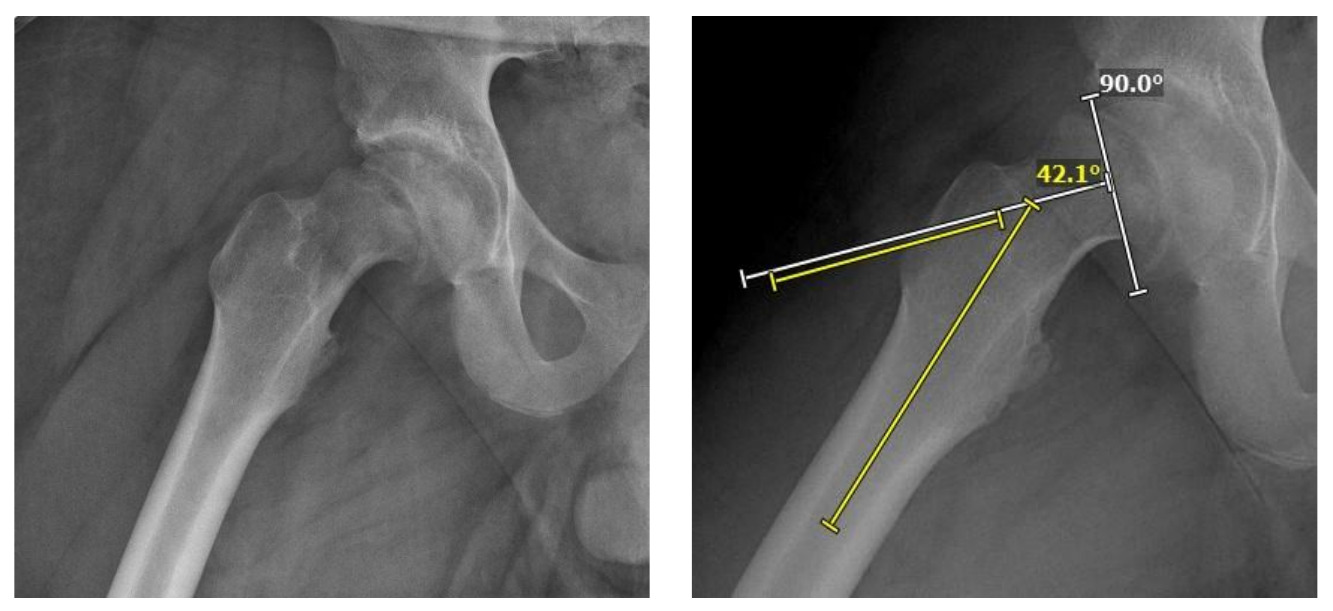

Typical presentation of SCFE is limping with gradual onset of pain 80-86% of the time and acute or acute on chronic pain 14-20% of the time (Matava et al. 1999). Pain usually occurs in the groin but presents 15% to 50% of the time as distal thigh pain or knee pain (Matava et al. 1999). This pain is exacerbated by activity and relieved with rest. 2/3 of SCFE patients are obese. There is decreased internal rotation and abduction of the hip, as well as obligate external rotation with hip flexion. In unilateral SCFE cases, there may be a leg length discrepancy. A lateral X-ray of the hip demonstrates an anteriorly subluxed femoral neck relative to the femoral head (Gholve, Cameron, and Millis 2009). In SCFE, Klein’s line will have little to no intersection with the epiphysis (Figure 3). SCFE is classified according to the percentage of the slip: mild if the displacement is less than 30% of the width of the femoral neck, moderate if between 30%-60, and severe if over 60%. The Southwick Angle or Head-Shaft Angle also classifies the slip: mild if the angle is 0-29 degrees, moderate if 30-50 and severe if >50. A technetium bone scan may demonstrate increased uptake of the femoral physis. The most sensitive test for SCFE is an MRI, which can detect physeal abnormalities prior to slippage. On the STIR sequence marrow edema will be seen within the physeal plate.

Radiographs including AP pelvis, AP and lateral (frog leg) of both hips demonstrated skeletal maturity at the stage of Risser 1 with closed triradiate cartilage and open proximal femoral physis of both hips (Figure 1). The right hip revealed a slipped capital femoral epiphysis with a disrupted Klein’s line and Southwick angle of 42.1 (Figures 2-7). Thus, due to his radiographs as well as his two weeks of inability to bear weight, he was found to have an acute-on-chronic unstable SCFE on the right.